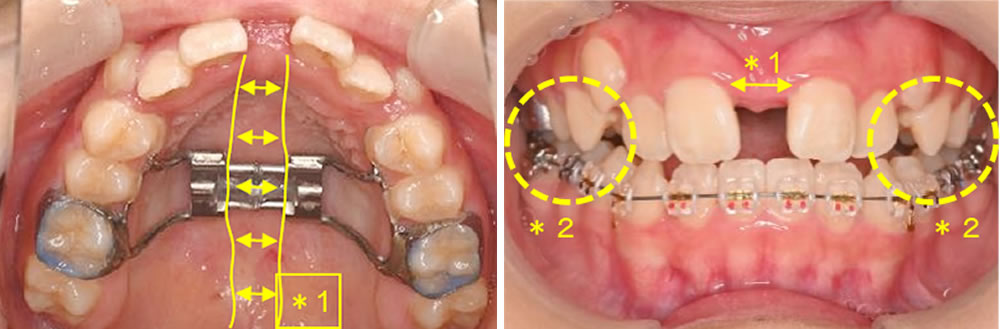

【急速拡大装置(RPE)の装着】

1日2回、装置の中央のネジを回し正中口蓋縫合を広げていきます。

※回す日数は患者さんそれぞれで異なります。

【矯正開始から3週間程度:歯列の拡大と臼歯反対咬合の改善】

(*1)正中口蓋縫合が広げられた分、上顎歯列も広がり、前歯も開いてきます。

(*2)反対になっていた奥歯の咬み合わせが改善されました。